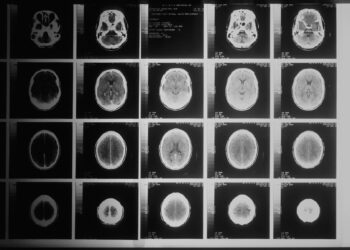

Καναδάς: Μεγάλη ανησυχία για εγκεφαλική νόσο που «χτυπά» νέους – Απαγόρευσαν σε ειδικό την έρευνα

Συναγερμός στην ιατρική κοινότητα του Καναδά, για άγνωστη εγκεφαλική ασθένεια, που είχε προσβάλλει περισσότερους από 200 ανθρώπους. Συγκεκριμένα, σύμφωνα με δημοσίευμα ...